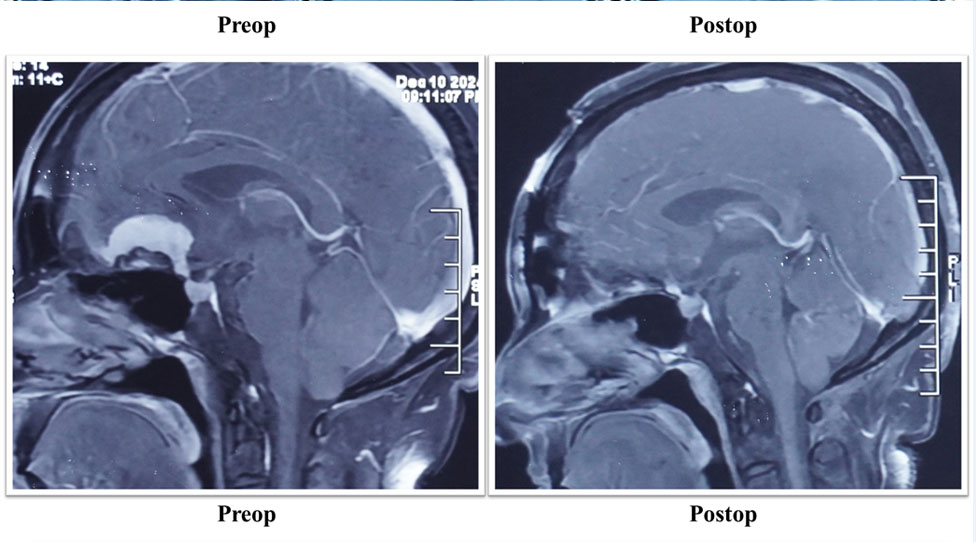

Moving ahead from facial preservation, hearing preservation in acoustic surgery always remains a challenge. With a good Cochlear nerve preservation rate and preserving useful hearing in almost one third cases, here I am presenting my latest case.

Though here, salvageable hearing was not present even in pre-op, but post-op Audiogram is showing absolutely untouched Cochlear nerve.